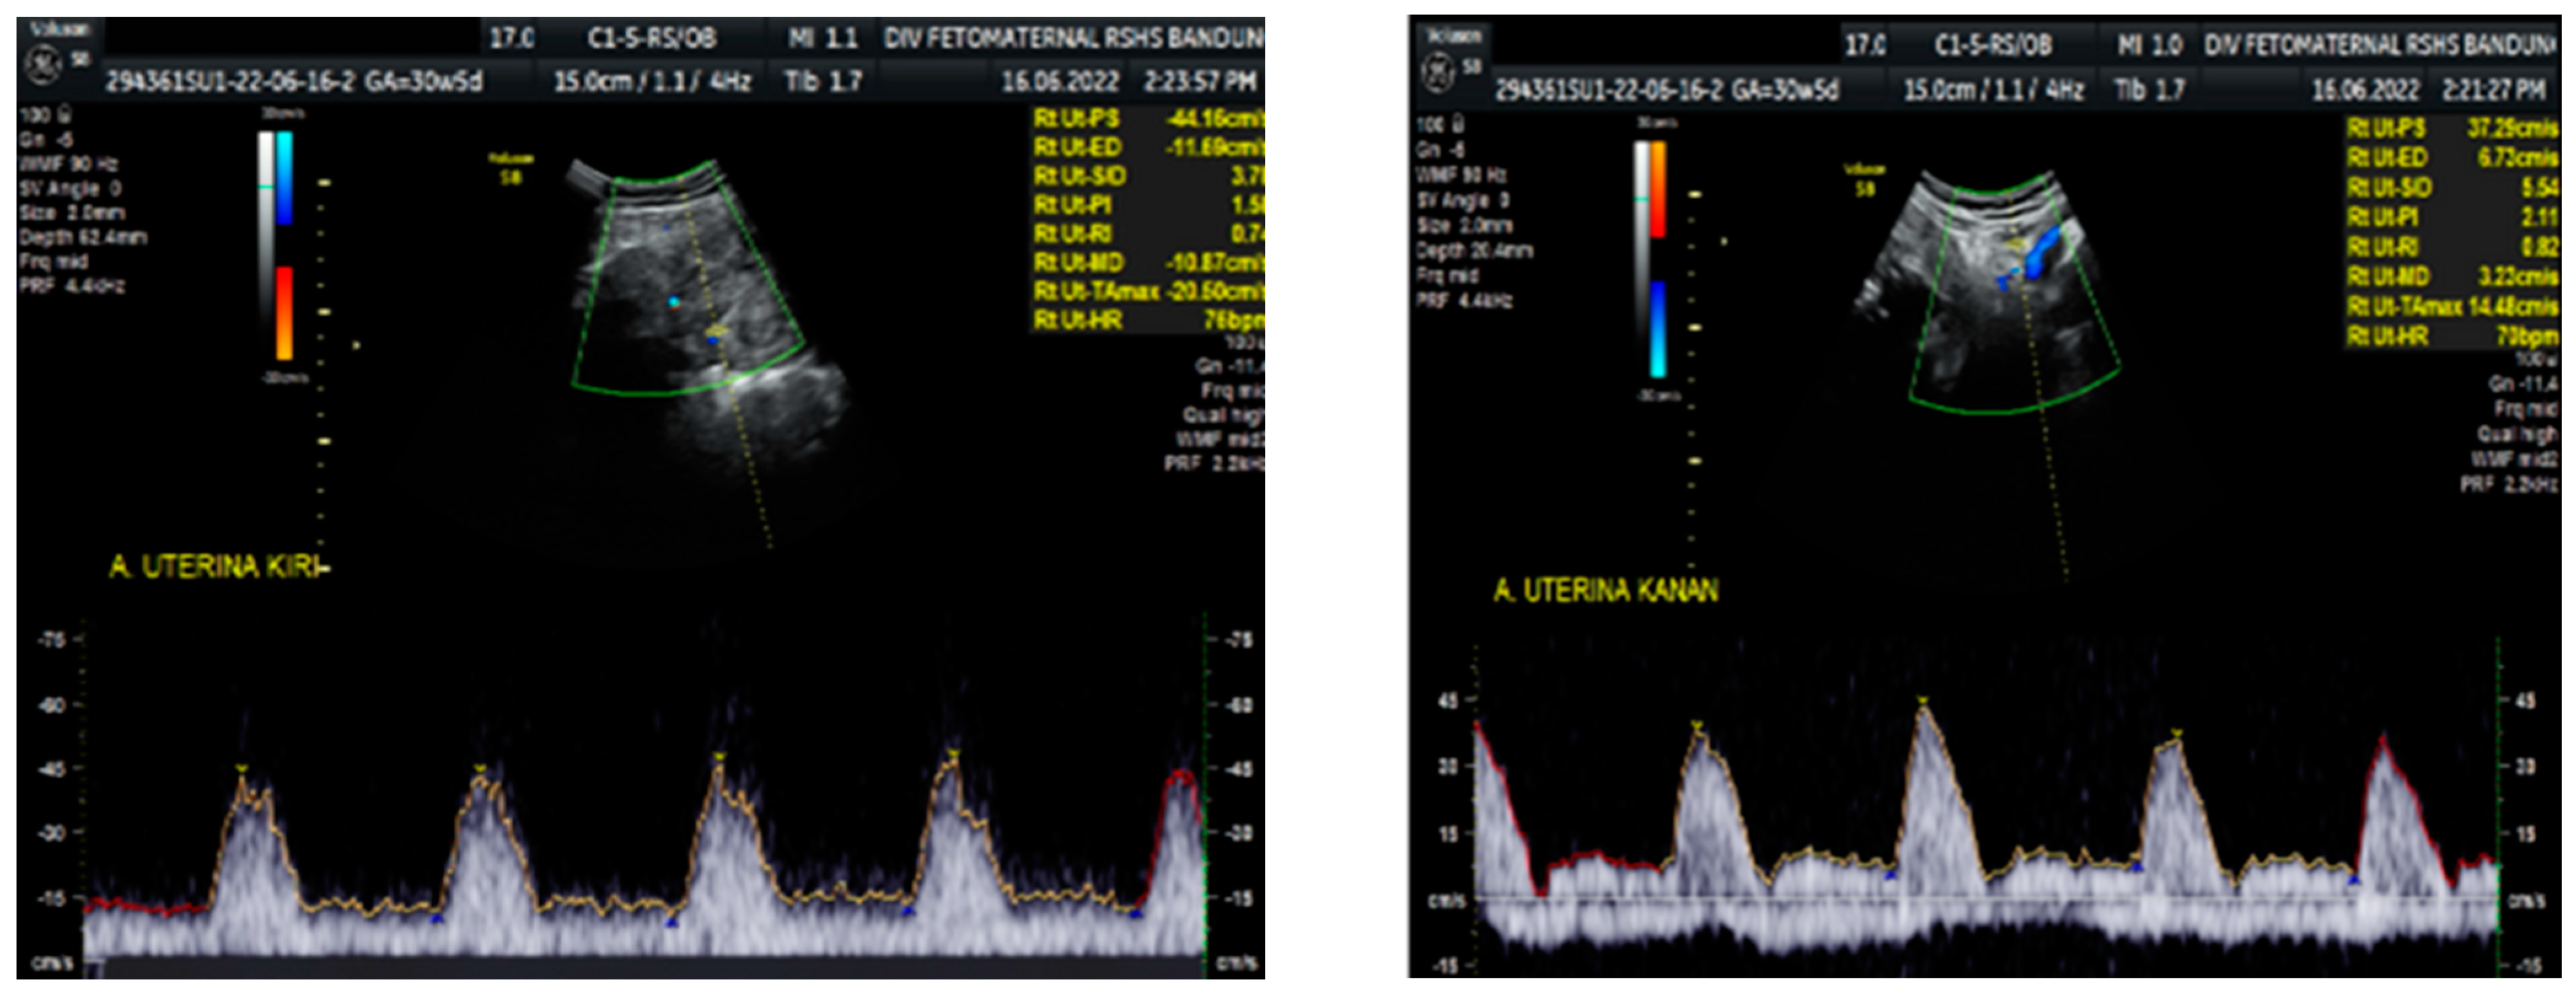

Figure 2. Reversed end diastolic flow in the middle cerebral artery.

Color Doppler examination of the MCA revealed a peak systolic velocity of 42.33 cm/s, which is 1.045 times the median (the normal range is 40.5 cm/s for this gestational age), with persistent reversed end diastolic flow (Figure 2). The umbilical artery pulsatility index (PI) was 0.99, and RI was 0.63, with an S/D ratio of 2.71. There was notching on the right uterine artery, with a PI of 2.11. Notching was also found on the left uterine artery, with a PI of 1.58 (Figure 3). Laboratory results were within a normal range.